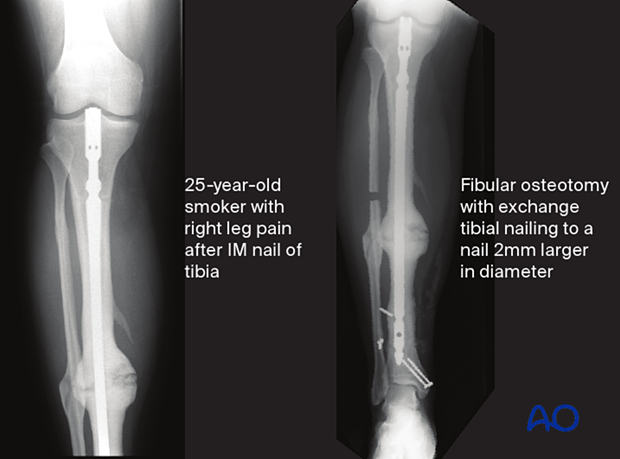

The image on the left shows a case of a young man, a Type B host, who required smoking cessation education when he had his original trauma. He developed a presumed aseptic hypertrophic nonunion of a diaphyseal tibia fracture that underwent IM nailing. The nail was removed, and a short segment of fibula was excised. The tibia was re-nailed after reaming to a larger diameter nail. The reamings were sent for culture and came back positive. Appropriate antibiotics were given for 6 weeks after surgery. The tibia healed without complication.